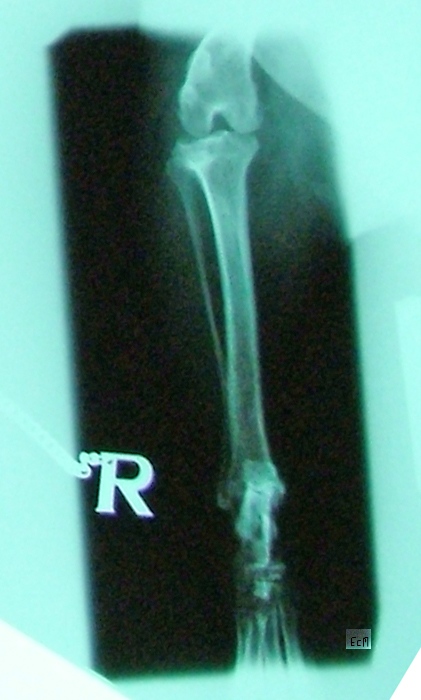

X-ray images of Charlie's leg. 2007